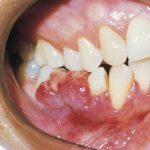

A reactive overgrowth of exuberant granulation tissue possibly in response to local irritation or trauma. This vascular mass often is ulcerated and may be smooth or lobulated and pedunculated or sessile.